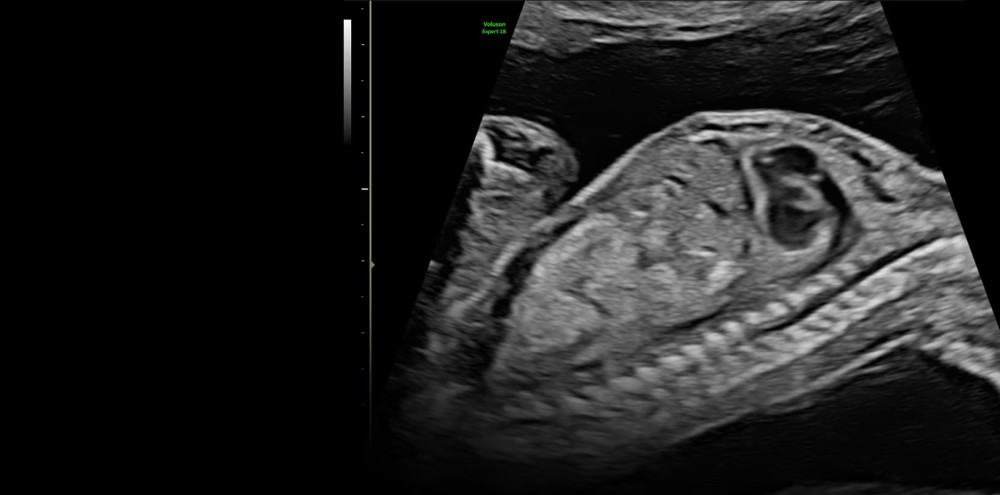

GE Voluson Expert 18 ultrasəs sistemi, xüsusilə mürəkkəb obstetrik və ginekoloji diaqnostika üçün nəzərdə tutulmuş yüksək performanslı diaqnostik platformadır və ultrasəs görüntüləməsində yeni klinik standartlar müəyyən edir. İnkişaf etmiş Lyric Architecture texnologiyası sayəsində cihaz yüksək məkan və kontrast ayırdetmə qabiliyyəti, aydın və homojen təsvirlər təqdim edir, bu da 2D/3D/4D volumetrik görüntüləmə ilə dəqiq və etibarlı klinik diaqnostikanı təmin edir.

Sistem süni intellekt əsaslı SonoLyst moduluna malikdir ki, bu modul fetal anatomiyanı avtomatik identifikasiya edir, müvafiq ölçmələri optimallaşdırır və rutin müayinələrin standartlaşdırılmasını təmin edərək vaxt qənaəti və diaqnostik ardıcıllığı artırır.

Rəngli Doppler, inkişaf etmiş volumetrik görüntüləmə və SonoPelvicFloor funksiyaları cihazın erkən fetal və pelvik patologiyaların aşkarlanması, müdaxilələrin planlaşdırılması və klinik qərarların verilməsi üçün yüksək detal və dəqiqlik təmin etməsinə imkan verir. Bu xüsusiyyətlər Voluson Expert 18-i qadın sağlamlığı sahəsində hərtərəfli və etibarlı ultrasəs diaqnostikası üçün optimal alətə çevirir.